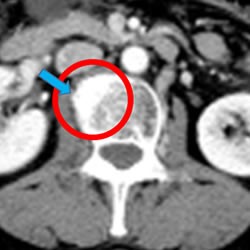

胃癌案例( 油门+刹车 疗法 2疗程 转移部位 消失,缩小)

胃癌转移(53岁 男性)癌症免疫疗法+抗PD-1抗癌剂2疗程

通过朋友的介绍开始了治疗。 肺.淋巴结.肾上腺.有转移.当时进行了1年半的抗癌剂治疗.但是转移部位的肿瘤越来越大.当时的主治医生建议.使用更强的抗癌剂.但是因为有着强烈的副作用所以没有进行.进行的是NK和抗PD-1抗癌剂疗法.2回的治疗.之后CT检查中越来越大的 肺部肿瘤消失.肾上腺.淋巴结也变小了.目前.以中断抗癌剂治疗.没有任何副作用.稳定的状态.

治疗前 治疗进行后